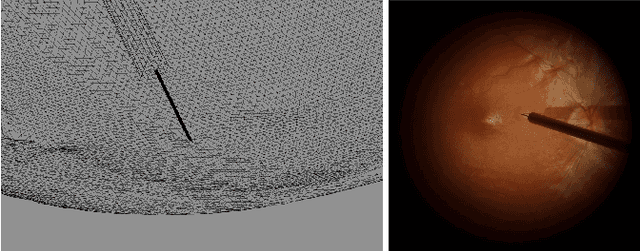

Abstract:Robotic platforms provide repeatable and precise tool positioning that significantly enhances retinal microsurgery. Integration of such systems with intraoperative optical coherence tomography (iOCT) enables image-guided robotic interventions, allowing to autonomously perform advanced treatment possibilities, such as injecting therapeutic agents into the subretinal space. Yet, tissue deformations due to tool-tissue interactions are a major challenge in autonomous iOCT-guided robotic subretinal injection, impacting correct needle positioning and, thus, the outcome of the procedure. This paper presents a novel method for autonomous subretinal injection under iOCT guidance that considers tissue deformations during the insertion procedure. This is achieved through real-time segmentation and 3D reconstruction of the surgical scene from densely sampled iOCT B-scans, which we refer to as B5-scans, to monitor the positioning of the instrument regarding a virtual target layer defined at a relative position between the ILM and RPE. Our experiments on ex-vivo porcine eyes demonstrate dynamic adjustment of the insertion depth and overall improved accuracy in needle positioning compared to previous autonomous insertion approaches. Compared to a 35% success rate in subretinal bleb generation with previous approaches, our proposed method reliably and robustly created subretinal blebs in all our experiments.

Abstract:In the last decade, various robotic platforms have been introduced that could support delicate retinal surgeries. Concurrently, to provide semantic understanding of the surgical area, recent advances have enabled microscope-integrated intraoperative Optical Coherent Tomography (iOCT) with high-resolution 3D imaging at near video rate. The combination of robotics and semantic understanding enables task autonomy in robotic retinal surgery, such as for subretinal injection. This procedure requires precise needle insertion for best treatment outcomes. However, merging robotic systems with iOCT introduces new challenges. These include, but are not limited to high demands on data processing rates and dynamic registration of these systems during the procedure. In this work, we propose a framework for autonomous robotic navigation for subretinal injection, based on intelligent real-time processing of iOCT volumes. Our method consists of an instrument pose estimation method, an online registration between the robotic and the iOCT system, and trajectory planning tailored for navigation to an injection target. We also introduce intelligent virtual B-scans, a volume slicing approach for rapid instrument pose estimation, which is enabled by Convolutional Neural Networks (CNNs). Our experiments on ex-vivo porcine eyes demonstrate the precision and repeatability of the method. Finally, we discuss identified challenges in this work and suggest potential solutions to further the development of such systems.